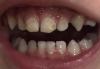

Как лечат кариес в начальной стадии под севораном?

врач пишет это кариес 😫

фото в комментариях

Конечно кариес, сколько ребёнку лет?у старшего с внутренней стороны так,но мы не лечим,он медленно прогрессирует и скоро выпадут эти зубы

Да, это кариес

Младшему в марте лечили под севоран. Но у него были еще хуже, чем у вашего ребенка. У вас кажется можно обойтись без севорана

Да это кариес